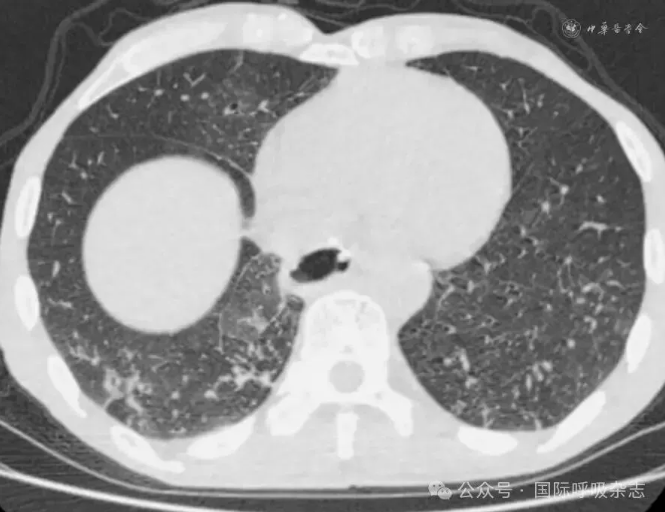

患者男,61岁,因“食管癌术后3年,咳嗽、气喘半年”于2025年3月14日入院。患者于2022年确诊食管鳞癌,曾接受新辅助免疫联合化疗、食管癌根治术、术后辅助免疫治疗、局部放疗及多线化疗等规范治疗。2024年12月经胃镜检查确诊为“气管食管瘘”,遂行空肠营养管置入术(图1)。后因咳嗽、气喘症状持续,辗转多家医院治疗效果不佳就诊于西安市胸科医院。入院查体:端坐呼吸,声音嘶哑,双肺可闻及湿性啰音及喘鸣音。实验室检查示炎症指标升高:白细胞计数8.82×109/L,中性粒细胞比例88.8%,C反应蛋白165.88 mg/L。血气分析pH值7.435,PaCO2为45.2 mmHg(1 mmHg=0.133 kPa),PaO2为55 mmHg,氧合指数200 mmHg,提示Ⅰ型呼吸衰竭。胸部CT提示气管食管瘘,伴双下肺感染及实变(图2)。支气管镜下见气管中下段膜部菜花样新生物,新生物下方可见瘘口(图3)。

图2:61岁男性气管食管瘘患者胸部CT(2025年3月14日)示气管食管瘘,双肺下叶感染、实变